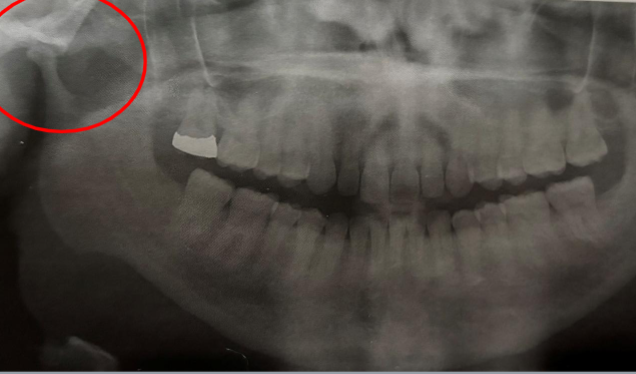

condylar hypoplasia

underdeveloped condyle